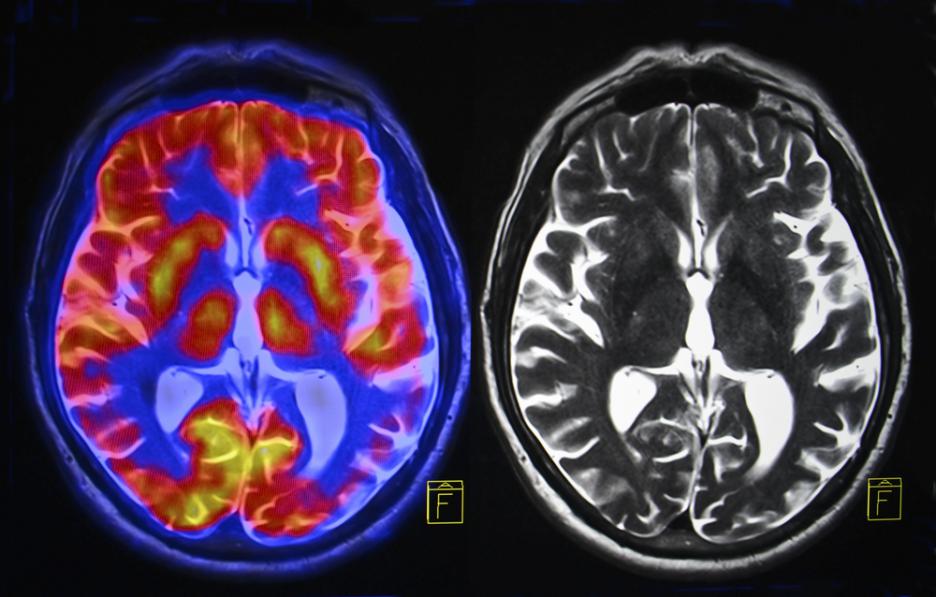

Използваме само 10 процента от мозъка си

Де да беше така! Томографските изследвания на мозъка и неврохиругията досега не са открили никакви "спящи зони". Твърдението най-вероятно датира отпреди век: психологът Уилям Джеймс заявил, че се съмнява дали средния човек използва и една десета от интелектуалния си потенциал. Всъщност съвременните изследвания показват, че непрестанно използваме много повече от 10% от нашето сиво вещество. Фактът е, че нито една област от човешкия мозък не е напълно пасивна винаги.